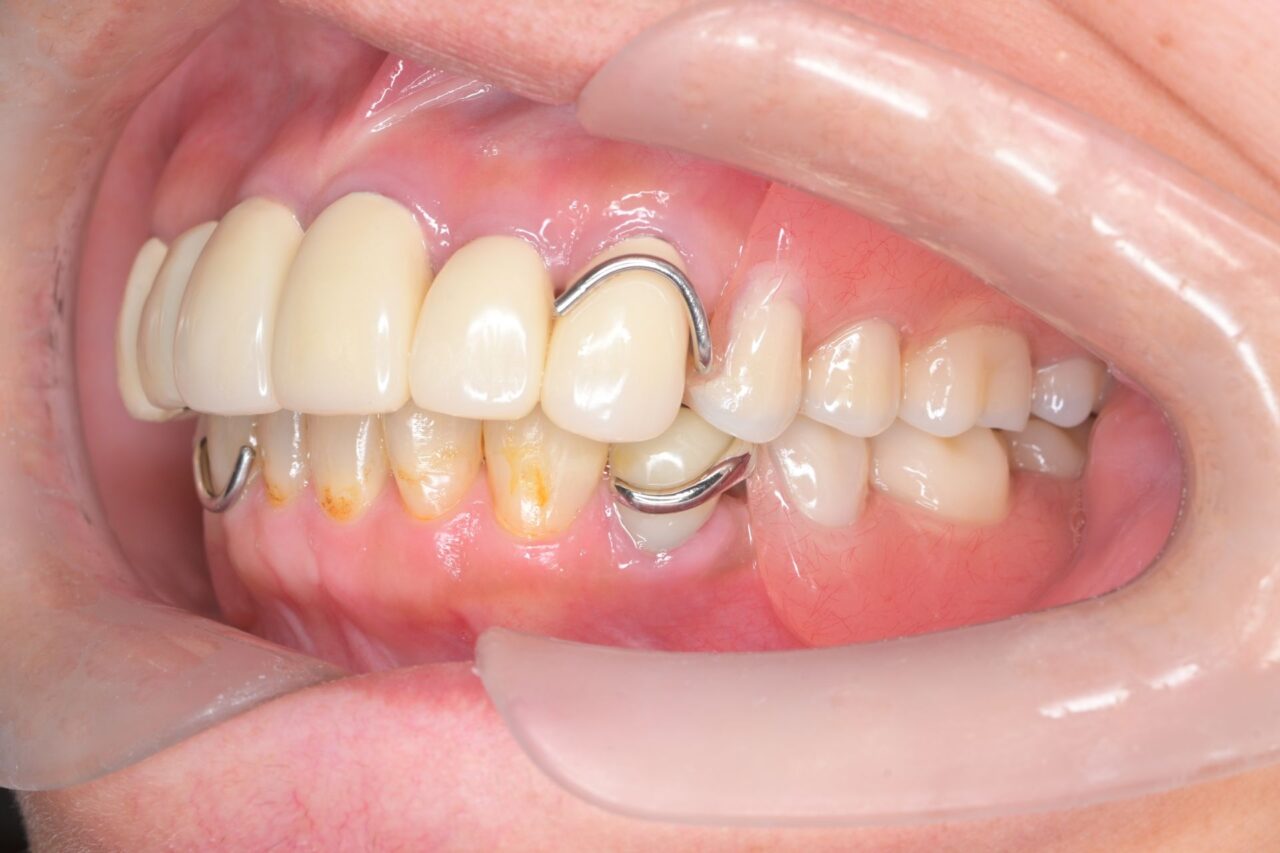

左側面

見えるところは全て白くしています。